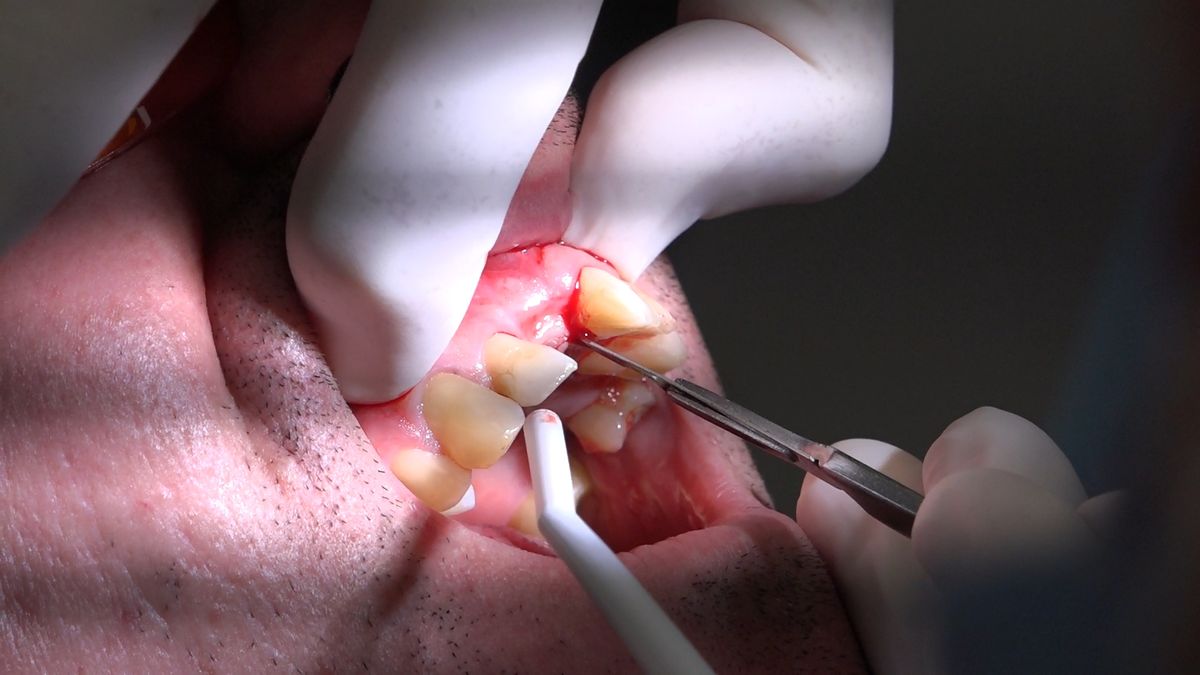

Practiculum Implantologii – Sezon VIIB, sesja 7, dzień 2